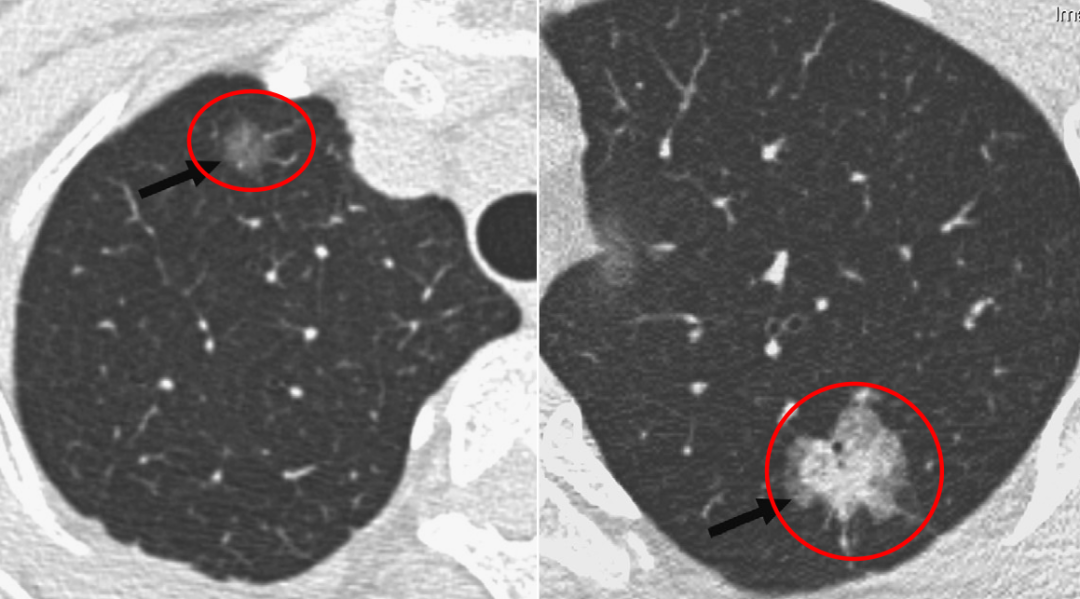

左图:纯磨玻璃结节;右图:部分实性的磨玻璃结节

其实大家比较担心的是部分实性的磨玻璃结节,右图的结节看起来就比左图「实」很多,大家一眼就能看到这个病灶。这个结节的实性成分很多,里面还有空泡、分叶和胸膜的牵拉。对于这个结节来说,有经验的医生一看可能就会觉得恶性程度比较大,所以对于这样的结节,医生会建议去做手术切除。因此,磨玻璃结节的表现的性质非常重要,不能从报告上完全读出来它究竟是恶性还是良性,还需要有经验的医生根据CT影像学的表现仔细辨别。